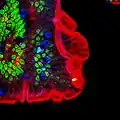

In mucicarmine stains, deep red mucin is found within goblet cell bodies. Goblet cells can be seen in the examples below as the larger, more pale cells.

An intestinal gland from the human intestine with goblet cells visible

An intestinal gland from the human intestine with goblet cells visible Goblet cell in ileum

Goblet cell in ileum Section of mouse intestine, mucus of goblet cells in blue

Section of mouse intestine, mucus of goblet cells in blue Goblet cells in large intestine

Goblet cells in large intestine